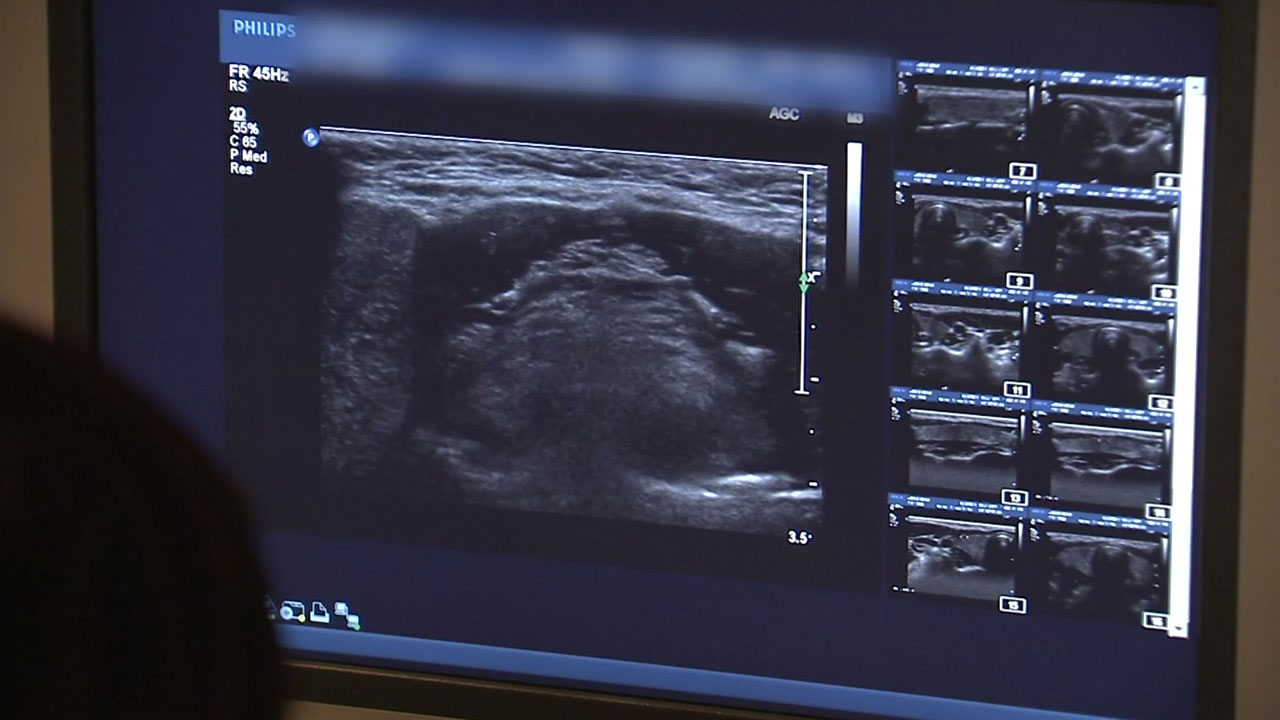

당장 올해부터 엑스레이(X-ray)와 씨티(CT) 같은 29종류의 의료 영상이 개개인의 신원을 가린 이른바 '가명화 작업'을 거쳐 기업에 무료로 공개됩니다.